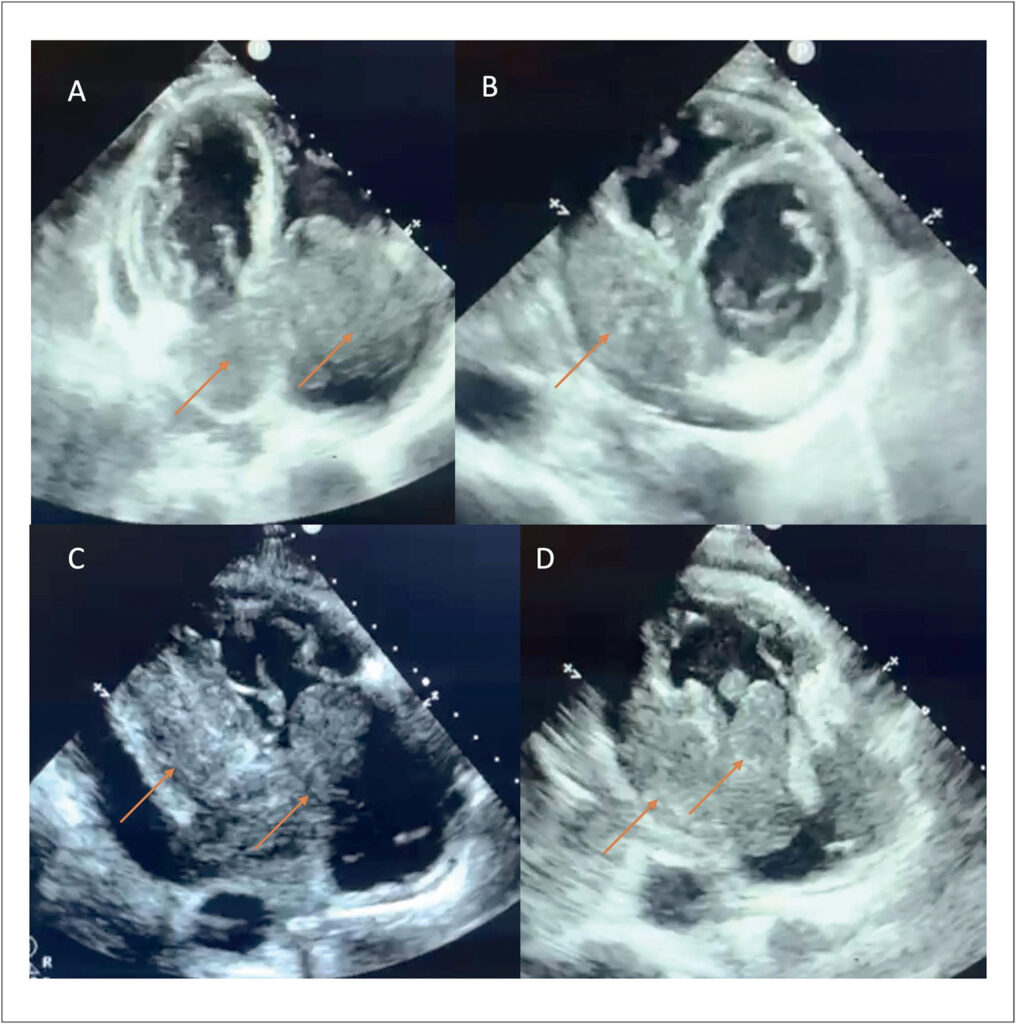

Primary cardiac lymphoma (PCL) is a rare and highly lethal neoplasm, whose nonspecific clinical presentation makes early diagnosis difficult. This article reports the case of an elderly patient, previously healthy, who experienced dizziness and syncope for four months before the discovery of a large tumor mass in the heart. Imaging exams, such as echocardiography and magnetic resonance imaging, were crucial for tumor identification, and the biopsy confirmed it to be a B-cell lymphoma with high replication. However, given the severity of the condition and the family’s refusal to proceed with treatment, the patient progressed to sudden death two weeks after diagnosis. Primary cardiac tumors (PCTs) are underdiagnosed, with varied symptoms that may include vascular obstructions, arrhythmias, and heart failure. PCLs account for only 1% to 2% of primary cardiac masses and are more common in elderly men. The diagnosis is challenging due to the absence of specific signs, making imaging exams and biopsies essential for disease confirmation. This case illustrates the complexity of managing PCLs, whose rapid progression limits therapeutic options. The lack of specific symptoms and silent progression highlight the importance of early diagnosis. The high mortality rate reinforces the need for greater medical attention to this condition, which frequently leads to fatal outcomes before an effective intervention can be implemented.